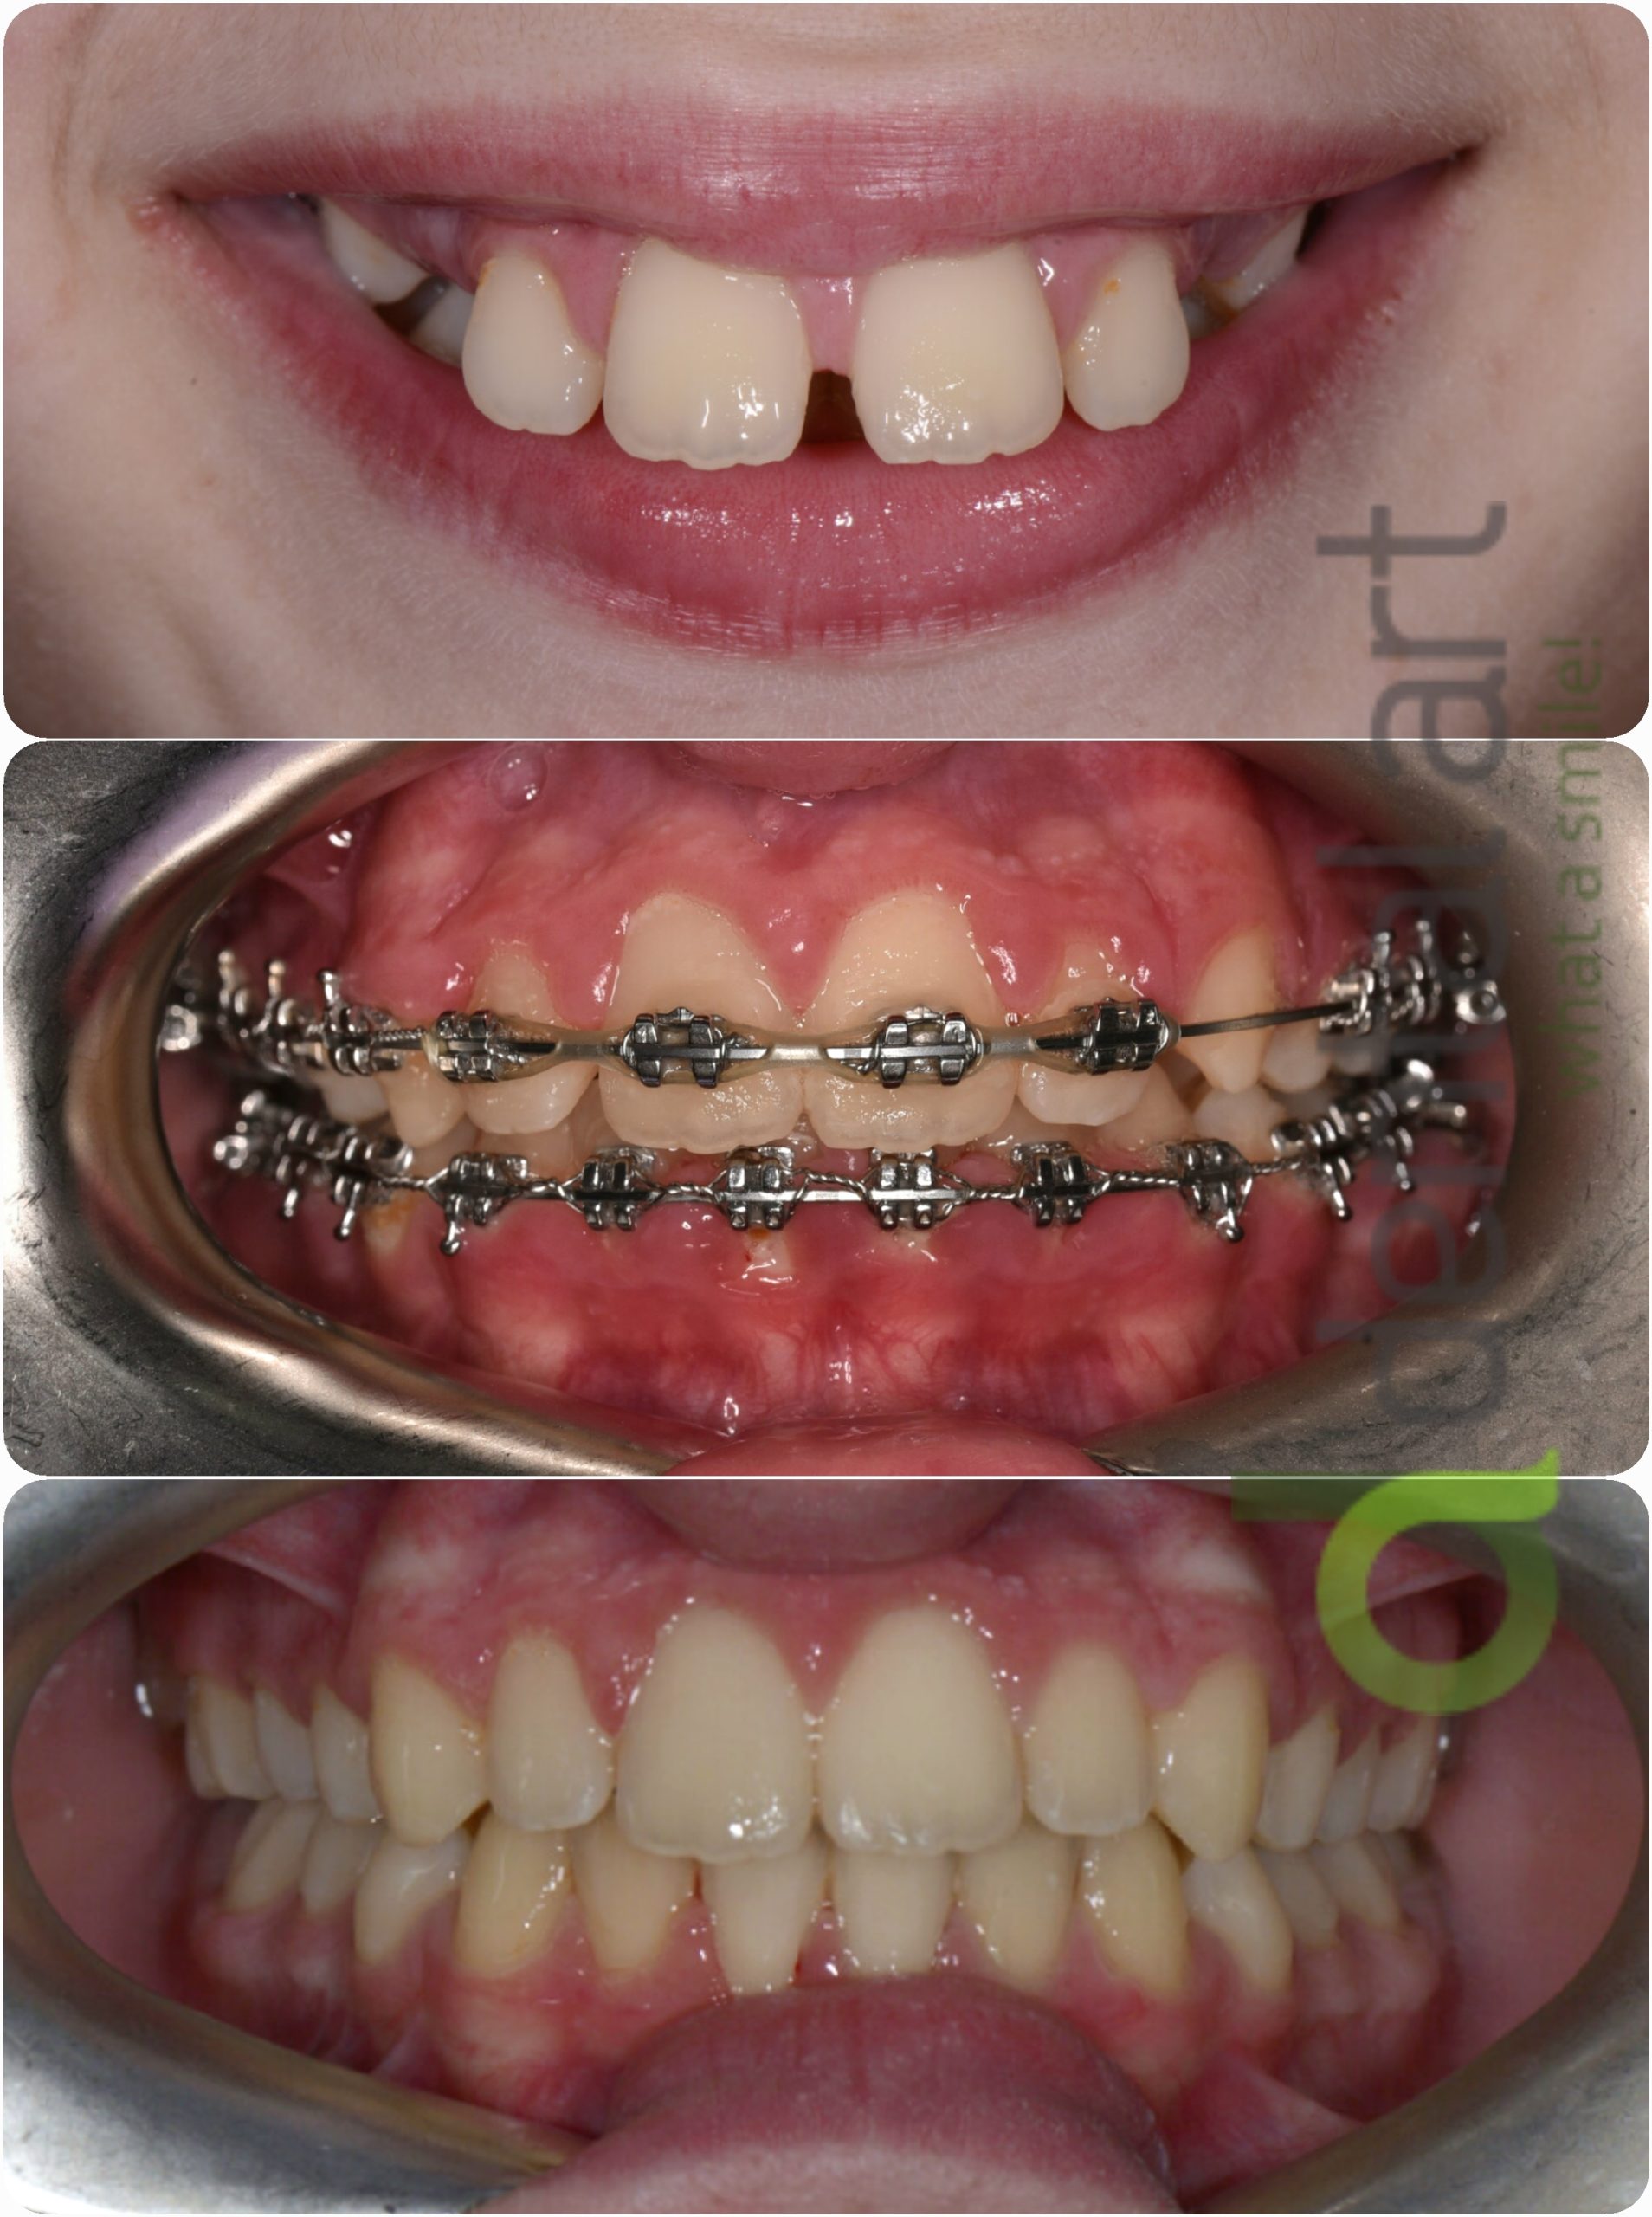

Aparat ortodontic fix - metalic

Este cel mai frecvent utilizat tip de aparat ortodontic, format din bracket-uri metalice lipite pe fața dinților permanenți cu ajutorul unui adeziv special. Bracket-urile sunt conectate printr-un arc metalic care exercită presiune asupra dinților pentru a-i deplasa în poziția corectă.

Beneficii: eficient, cel mai accesibil ca preț

Dezavantaje: vizibil, poate cauza disconfort inițial